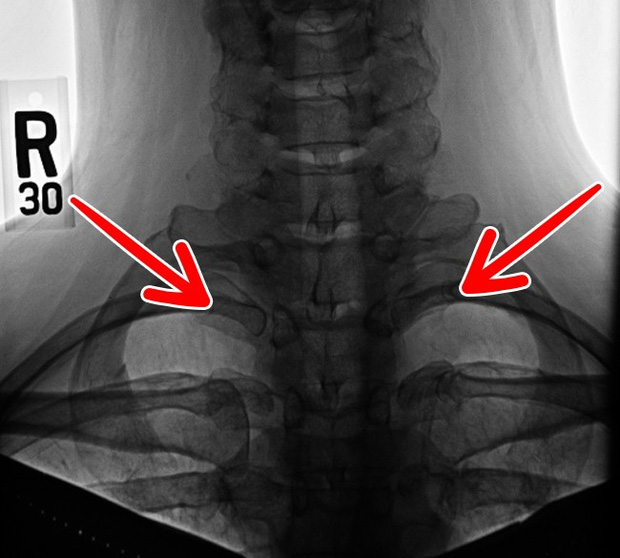

4. Xương sườn cổ biến mất

Có khoảng 1 - 3% dân số thế giới phát hiện sở hữu 1 chiếc xương sườn thừa, gọi là xương sườn cổ. Nó nằm ở ngay phía trên xương đòn.

Có người có xương sườn cổ ở bên trái, người thì ở bên phải, và cũng có người sở hữu ở cả 2 bên. Tuy nhiên, đôi khi chúng được tạo ra không thật đầy đủ, thậm chí mỏng như vài sợi vải.

Dẫu vậy, chúng có thể chèn ép mạch máu, dây thần kinh quanh cổ dẫn đến cơn đau cổ, vai... Nhưng thật mừng là chúng có thể biến mất trong tương lai.